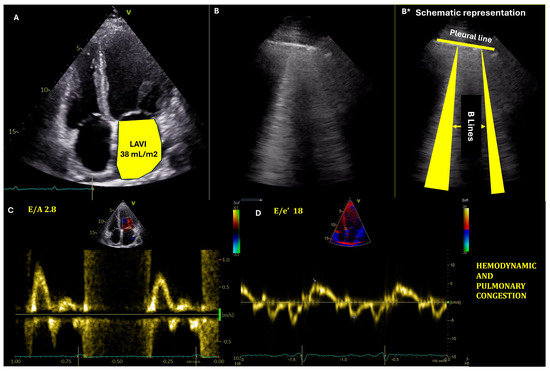

Echocardiographic estimation of LV filling pressures (Figure 1) has become an indispensable tool in the management of HF patients (Appendix B, Table A3). The integration of multiple parameters, including left atrial volume indexed (LAVI), E/e’ ratio, and tricuspid regurgitation velocity, provides a more comprehensive assessment of congestion. Pre-discharge echocardiography, in particular, has demonstrated significant prognostic value and can optimize discharge timing and post-discharge care planning [72,73].

Assessment of hemodynamic and pulmonary congestion with echocardiography and lung ultrasound. (A) Transthoracic echocardiography, four-chamber view depicting dilated left atrium. (B,B*): Lung ultrasound with lung congestion—presence of B-lines (laser-like artefacts beginning at the pleural line and ending at the lower part of the interrogation sector). (C,D): Pulsed wave Doppler at the mitral valve and tissue Doppler tracing at the interventricular septum, respectively, showing increased left ventricular filling pressures.

LAVI is a robust indicator of chronic elevation in LVFP (Figure 2). An enlarged left atrium, typically defined as LAVI > 34 mL/m2, reflects long-standing pressure overload [74]. The prognostic value of LAVI has been demonstrated in various studies. For instance, a meta-analysis by Shin et al. showed that increased LAVI was associated with adverse cardiovascular outcomes in patients with HFpEF [73]. Nonetheless, its clinical application faces several challenges. LAVI changes may not occur rapidly enough to guide acute management decisions in ADHF, and conditions such as atrial fibrillation and significant mitral valve disease can affect LAVI, complicating its interpretation in ADHF. These confounding factors necessitate careful clinical correlation and potentially limit LAVI’s standalone diagnostic value [74,75].

The ratio of early mitral inflow velocity (E) to mean septal and lateral early diastolic mitral annular velocity (e′) is widely used to estimate LVFP. An E/mean e′ ratio > 14 (E/e′ ≥ 11 for atrial fibrillation) suggests elevated filling pressures [72,77].

LUS markers of congestion are B-lines and pleural effusion. While fluid in the pleural space represents a more severe marker of congestion, B-lines can be identified in the early stages of congestion and can guide rapid initiation of therapy. B-lines are easy to identify LUS artifacts; they appear as vertical, “laser-like” hyperechoic lines, starting from the pleural line and extending to the lower part of the interrogation sector, moving synchronously with the pleural sliding (Figure 1). Less than two B-lines per intercostal space can be identified in normal persons. However, an increasing number of B-lines will be present as interstitial lung edema appears [83]. The presence and quantity of B-lines on LUS correlate strongly with the degree of extravascular lung water and can accurately identify pulmonary edema [13].